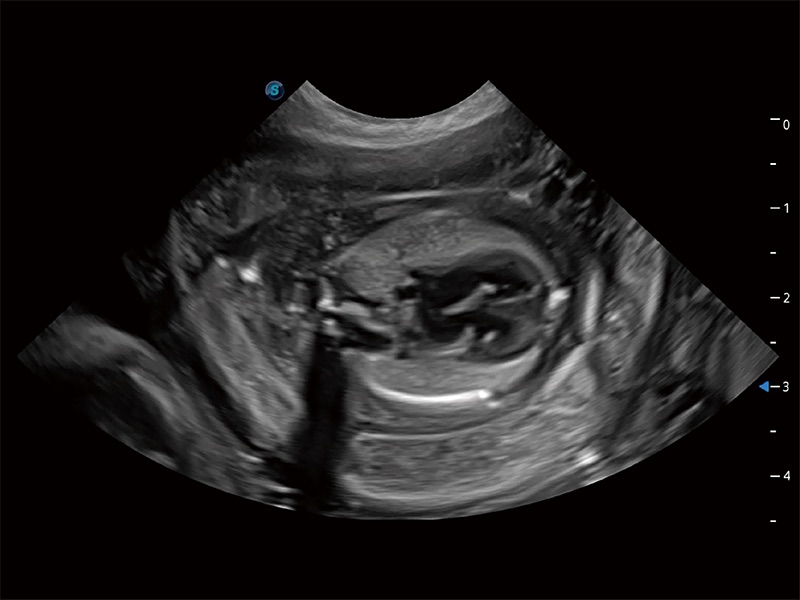

ProPet 80 专为动物医生设计,对不同的动物体型和生理结构作出了针对性的优化。通过动物影像专用软件,可满足个性化的应用需求,帮助动物医生获得更精确的诊断数据。

为精细结构及组织边缘提供高清晰度的图像和更大的成像视野。帮助减轻医生的用眼疲劳,快速精准获得测量的数据。

针对宠物、马科、农场动物、实验室动物和异宠等20多种动物种类,预置丰富的动物注释及动物体标库。

ProPet 80 全新的动物超声智能软件和丰富的探头群,为动物医生提供了高清晰度和精细分辨率的图像,无论在宠物、马科、畜牧还是实验室动物等应用中都可以轻松应对,为您的日常工作带来满意的体验。